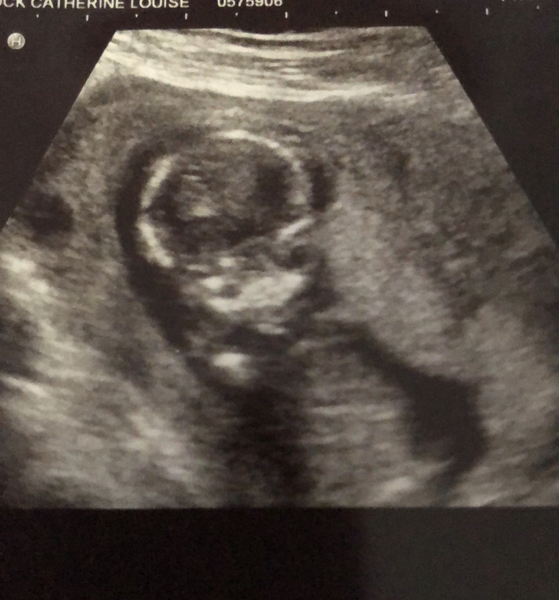

Thanks @Gummybear17 scan went great. Baby was in an awkward position but the picture we got is so cool with Halloween coming up…

We were shown between the legs but I couldn’t work it out. I read a girl looks like a hamburger and a boy like a turtle. Ours looked like an uncut burger bun so just a bulge. I guess it could be either. We booked a gender scan for two weeks time. Again the skull on this baby looks so much more dainty than ds so still wondering if a girl. Xx

@Catconfusion glad all went well! That picture is awesome! X

Thanks @Gummybear17 we got a similar one with our son at the same gestation. That was just before Halloween too…

The skull shapes look so different. I’m even more convinced this one is a girl. We will see! Xx